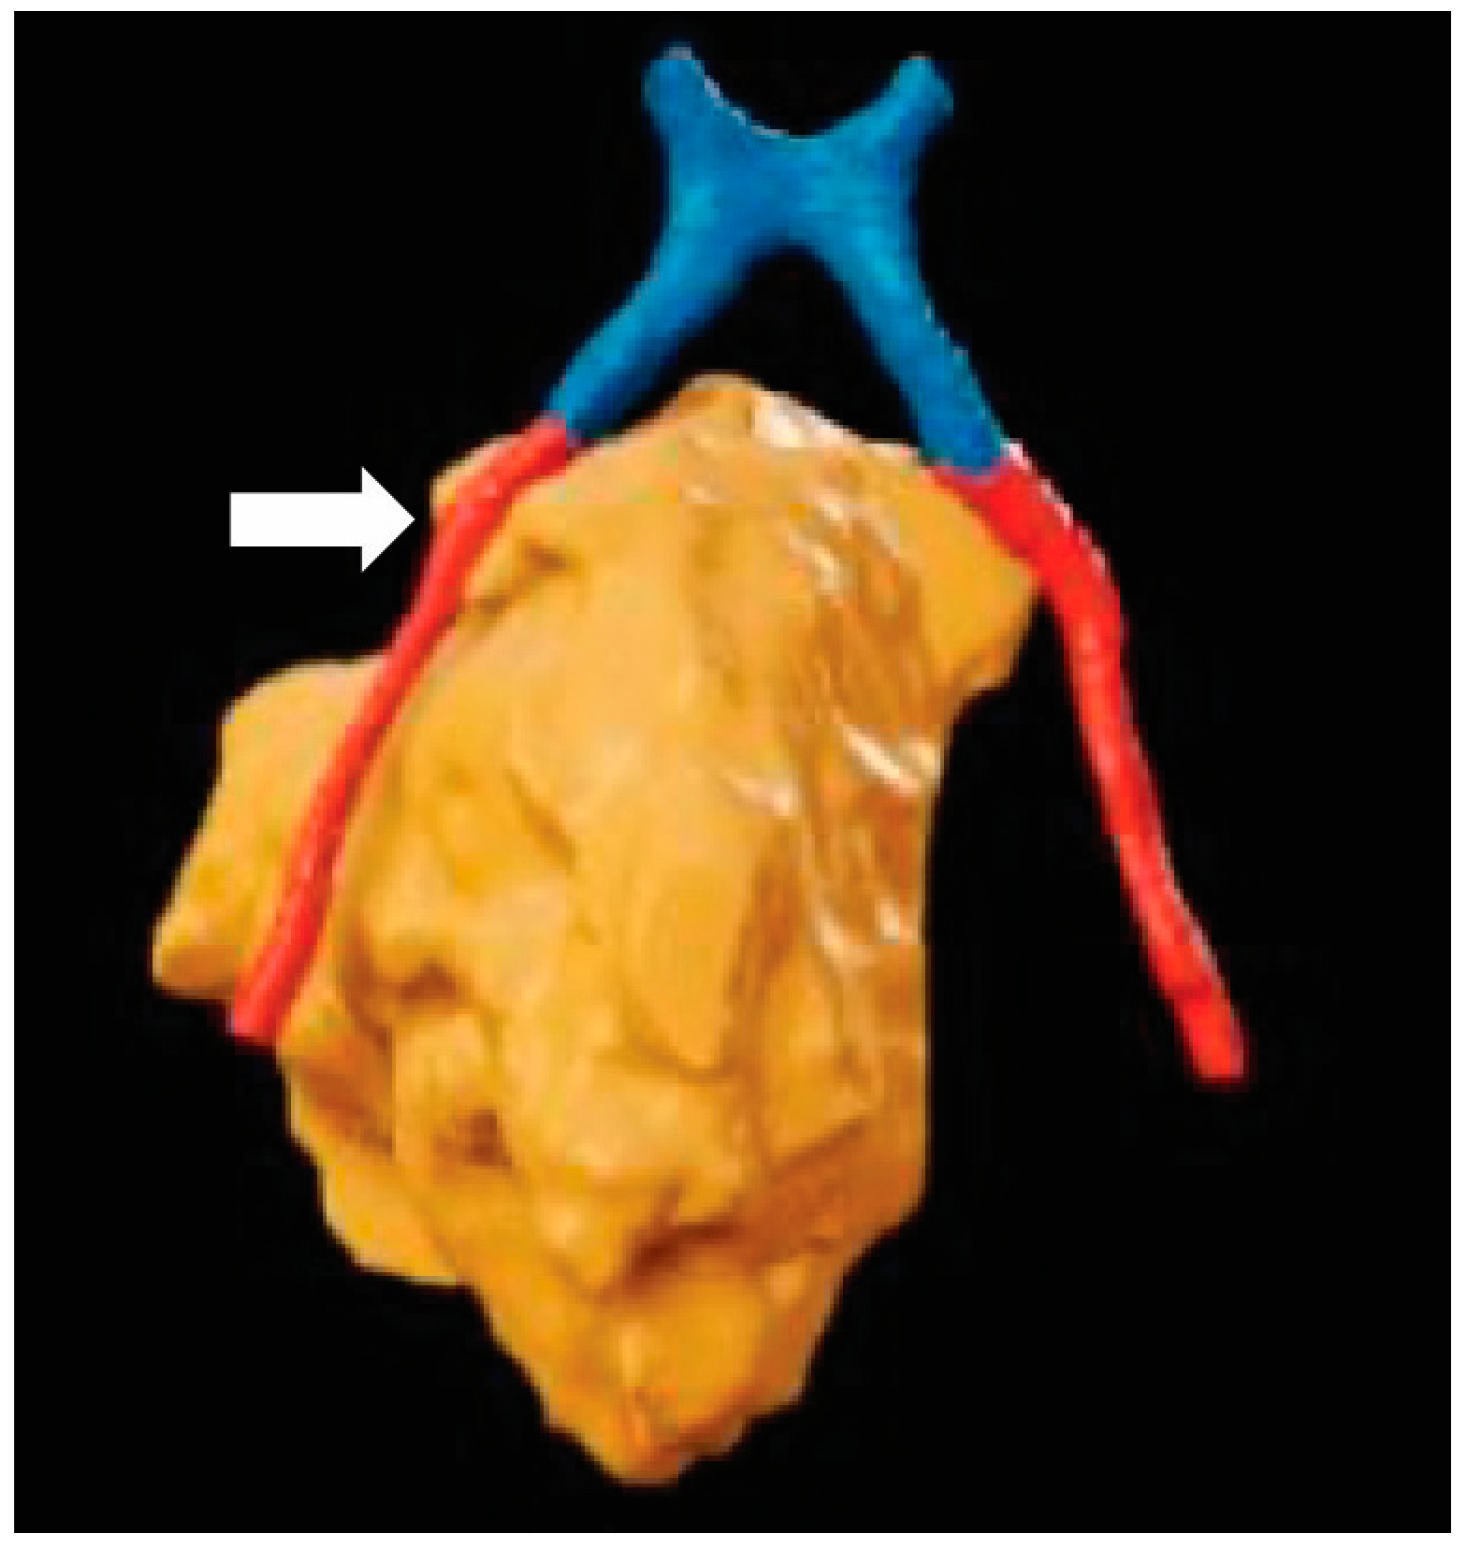

Figure 4. Surgical planning with XR: A top-down 3-dimensional reconstruction of the optic chiasm (blue), optic nerves (red), and esthesioneuroblastoma (orange). Although the right optic nerve approximates the tumor, there is no direct invasion (white). The reconstructed objects allow for clear visualization of the spatial relationship between anatomical structures that may impact surgical plans.